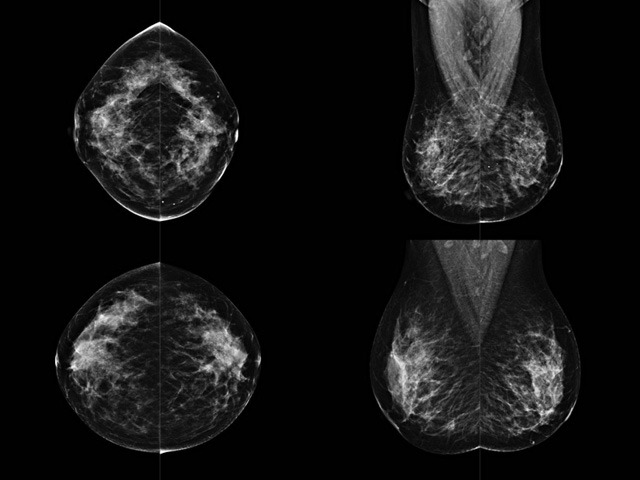

乳腺DR成像设备中非晶硅跟非晶硒两种平板探测器

乳腺DR成像设备中非晶硅跟非晶硒两种平板探测器。更要提供优质的图像质量乳腺的组织结构与厚度各不相同,减少重拍率辐射剂量,,乳腺的主要构成组织均为软组织结构,组织之间密度十分相似,缺乏天然对比度。选择软X线摄影技术获得良好对比度的乳腺结构影像。增加各组织对X线的吸收差异。乳腺摄影测和分类,平板探测器的像素尺寸范围应在50到100μm之间。特别是微钙化灶可以小到100到200μm,平板探测器都必极小微钙化灶进行成像。

乳腺DR是利用X光来做检查,在一瞬间将被检测到的位置投影出来,因为是瞬间的辐射,所以只需要0.5秒的时间。因此对病人的辐射很低,大约是0.023mSv,比国家的标准要低得多。DR系统由 X线、发生装置、直接转换平板探测器、系统控制器、影像监视器、影像处理工作站等组成。能检查胸腔积液、肺结核、大叶性肺炎、肋骨骨折等。心室增大、主动脉扩张、主动脉瘤等心脏病。腹部病变,如肠梗阻、肠穿孔等,DR上可见液气平面、膈下游离气肿。DR表现不正常,要结合临床表现、体征、症状等综合分析,结合CT、彩超、血液分析等,才能作出正确的判断。